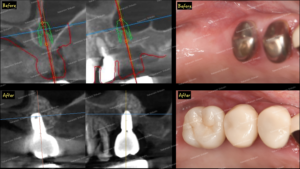

インプラントのシュミレーションについてです。写真のように、奥歯がない状態のところにインプラント治療を予定します。従来では入れ歯になりますが、入れ歯も違和感や当たりができて痛い、十分に噛めないなどのデメリットがありますので、それらを解決する方法にインプラント治療があります。

今回は従来の方法として、歯型をとり、模型上でシュミレーションを行いました。写真のように、歯がないところにワックスで歯の形、噛み合わせをシュミレーションします(青い歯が該当部分です)。今回は写真のように1箇所にインプラント治療を行うことになりました。

今回の場合、骨が細い部分があるため、インプラントのネジ部分が露出しています。本来はこのネジ部分は骨の中にあるべき部分です。この部分は骨の中に位置してほしい部分なので、この部分に骨再生療法、骨増生(GBR治療と言います)を施します。

人工骨とコラーゲン膜を用いて、骨再生治療を施します。これらによって、この出来上がったスペースに骨の細胞が骨を新生していきます。

写真のように、インプラントのネジ穴を確認できます。ここに、スキャンするようのパーツを装着します。

スキャンしたデータ画像です。昔なら、歯型をとり、石膏模型として口の状態を確認していきますが、近年はスキャンしたデータをパソコンで確認し、それを元に被せ物を作るという流れです。実際の口の中の状態とスキャンしたデータ画像の比べても、しっかりと読み取れていることがわかります。

実際に、口の中へと装着します。ネジ穴として空いていた穴は、プラスチックで封鎖します。言い換えると、この封鎖したプラスチックを削り取れば、インプラントの被せ物を外すことも可能です。

以上がインプラント治療の一連の流れです。今回は骨を増生、新生するという骨再生療法を併用した流れです。必ず骨再生を行うわけでなく、十分な状態であれば骨再生治療は行いません。